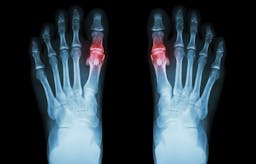

Can we blame gout’s resurgence on ketosis? I don’t call this a diet, but a new beginning

| Caries/Crooked teeth (3) | Gout (4) | Success story (190) |